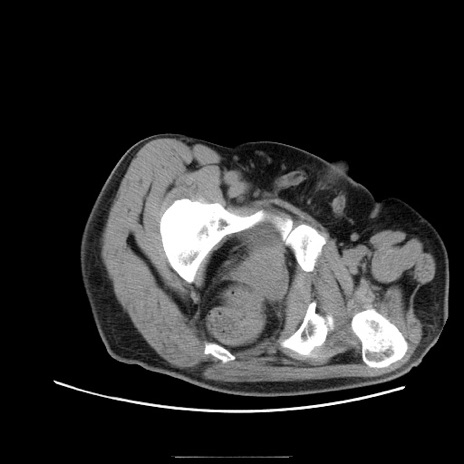

症例22(横断像)

【症例】50歳代男性

【主訴】腹痛

【現病歴】AVMからの被殻出血のため回復期リハ病棟入院中。 本日午後3時頃急に下腹部痛が出現した。

【既往歴】AVM、被殻出血、虫垂炎、高血圧

【身体所見】意識晴明、左半身不全麻痺、会話の理解は良好、36.5°C、腹部:膨隆、全体に板状硬、下腹部正中に圧痛点あり、反跳痛-、筋性防御不明、右下腹部にope scar

【データ】WBC 9400、CRP 0.06